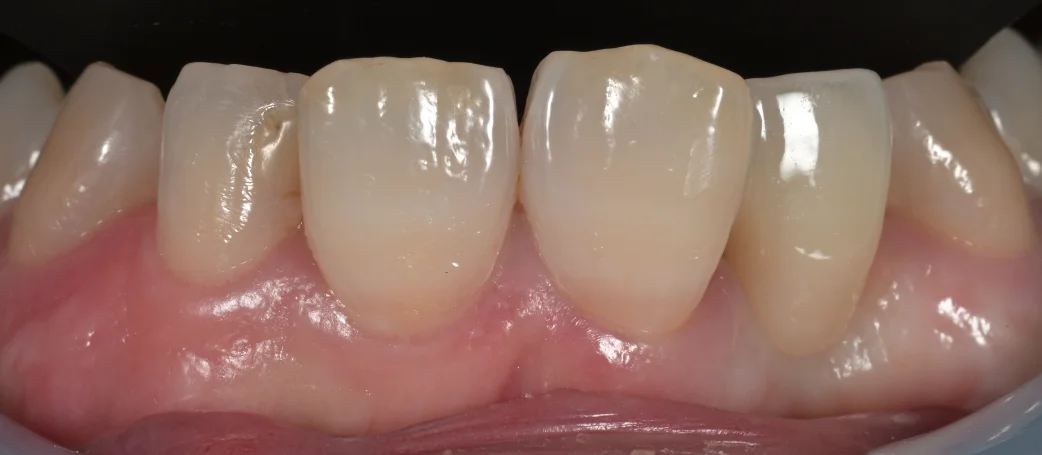

では今回どのように治療したのかというと・・・術後の写真がこちらになります。

こんな感じです。

元の歯はぱっと見ほとんど変わってないように見えますよね?

斜めから見たのがこちらになります。

セメントでつけた後にそのセメントを除去した時の写真です。

隙間も段差もなく綺麗にハマっているのがわかると思います。